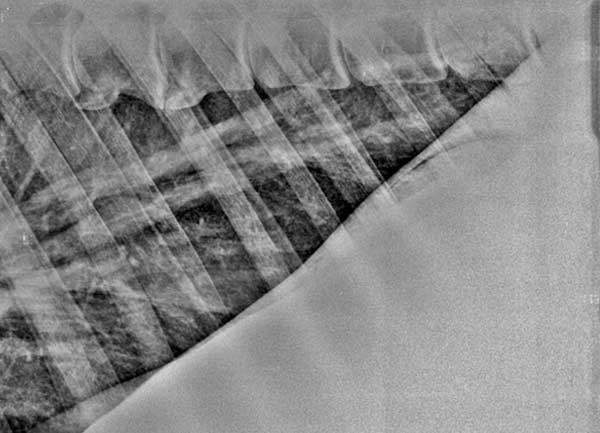

Röntgenfoto van longen van een paard met ernstige longproblemen: de luchtwegen zijn reeds "verlittekend".